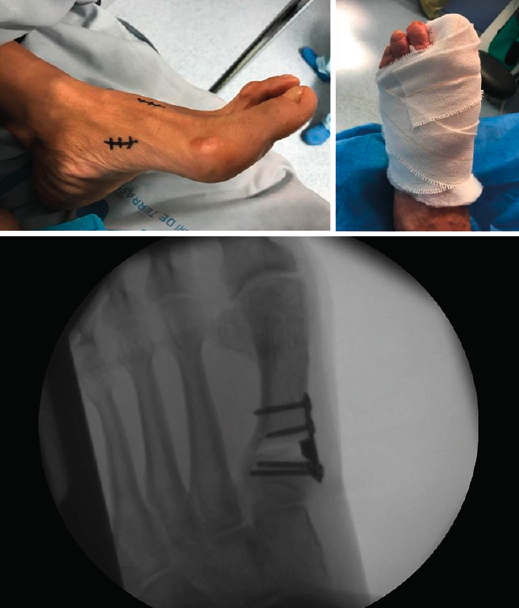

Figura 2. Detalles quirúrgicos de la osteotomía de apertura medial.

No se objetivó ningún caso de metatarsalgia de transferencia ni de pseudoartrosis. En las Figuras 2 y 3 se pueden ver detalles quirúrgicos de las osteotomías de apertura y cierre.